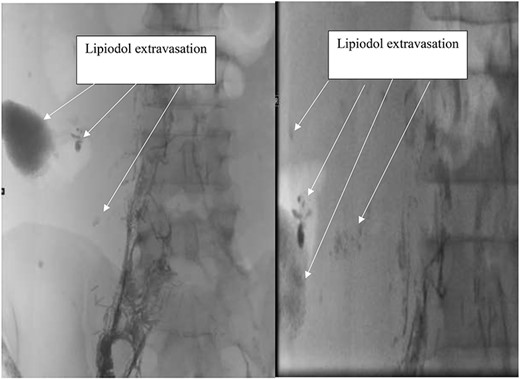

Follow up with the patient occurred one week later revealed recurrent chyle ascites. Failure of conservative management with the chyle diet prompted consultation with Interventional radiology for lymphangiography and possible lymph angioembolization. Imaging from lymphangiography with Lipiodol demonstrated pooling of contrast and lipiodol in the right lower quadrant, which favored the chyle leak site seen in Fig. 1. Two days later after lymphangiogram with lipiodol the leak was ceased, and the patient was discharged home.

Lymphangiogram with lipiodol showing Lipiodol extravasation at the site of chyle leak.

Lymphangiography may be used as a diagnostic and potential therapeutic approach for CA. Lymph angioembolization can also be utilized concurrently. Furthermore, lymphangiography alone has been shown to dramatically slow down or completely stop the chyle leaks in our cases. This is believed to be due to lipiodol accumulating at the point of leakage resulting in a regional inflammatory reaction occurring in the soft tissues adjacent to the lipiodol retention yielding embolization [11]. The viscosity of lipiodol is also thought to contribute to embolization.